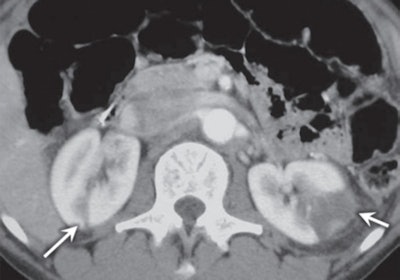

Genitourinary symptoms: Renal infarction, which tends to be more prevalent in men than in women and more common in the right kidney.